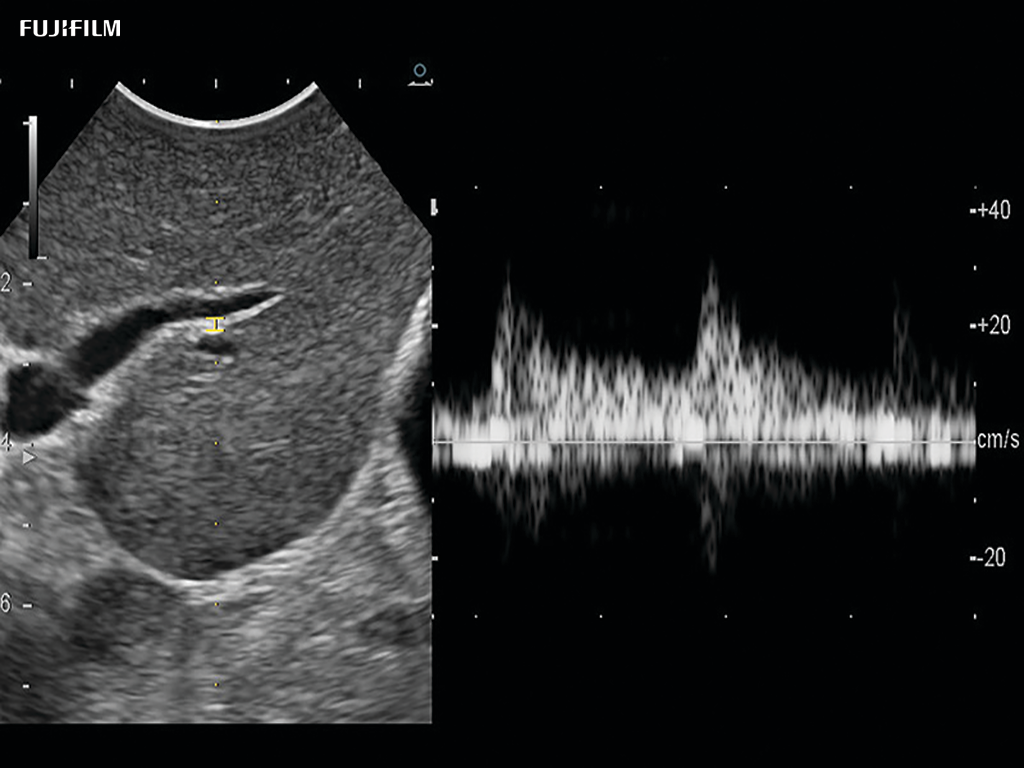

Liver Spectral Doppler using C22I

Curved array deep penetration “I” style finger-grip transducer for open kidney surgical procedures. Allows for palpating organs and scanning at the same time.